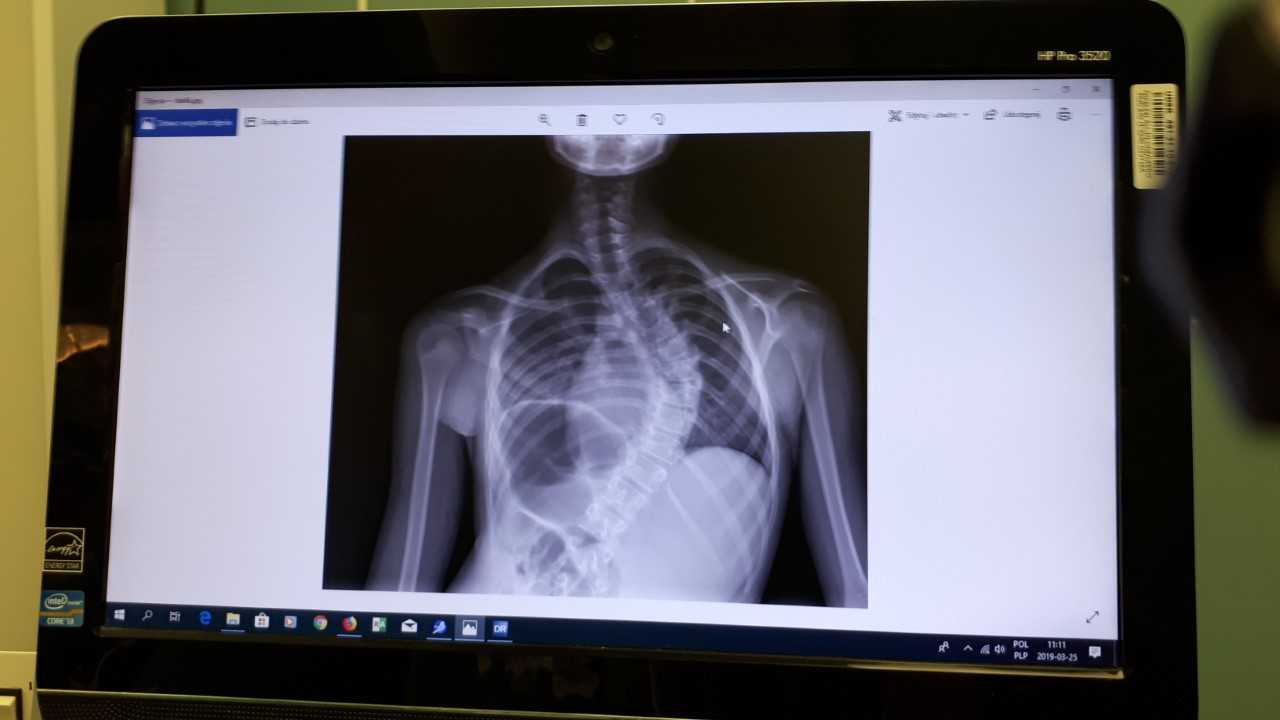

Pierwszą w Polsce operację bez usztywniania kręgosłupa u dziecka ze skoliozą przeprowadzono w poniedziałek (25.03) w Uniwersyteckim Dziecięcym Szpitalu Klinicznym w Białymstoku. Metoda ta pozwala w sześć tygodni wrócić pacjentowi do aktywności fizycznej.

Lekarze w Białymstoku przeprowadzili pierwszą w Polsce nowatorską operację skoliozy u dziecka, fot. Renata Reda

Operacji korekcji skoliozy idiopatycznej nowatorską techniką bez usztywniania kręgosłupa, tzw. VBT (ang. Vertebral Body Tethering), poddano 11-letnią dziewczynkę z Katowic. Operację przeprowadzili ortopedzi z Kliniki Ortopedii i Traumatologii Dziecięcej Uniwersytetu Medycznego w Białymstoku dr Paweł Grabala i dr Tomasz Guszczyn oraz światowej sławy chirurdzy kręgosłupa z USA dr Darryl Antonacci i prof. Randal Betz z Institute for Spine and Scoliosis (New Jersey) – poinformował Uniwersytet Medyczny w Białymstoku.